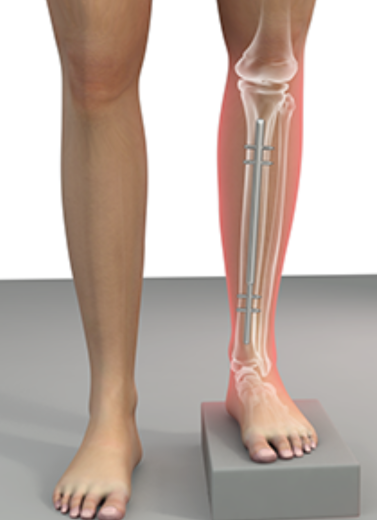

The Ilizarov method uses a circular external fixator to slowly correct bone shape or length. This technique promotes natural bone regeneration and reshaping by gradually adjusting tension and alignment over time. It allows correction without large surgical cuts or implants inside the body.

Ilizarov Technique for Limb Lengthening & Deformity Correction

External Fixators & Circular Frames